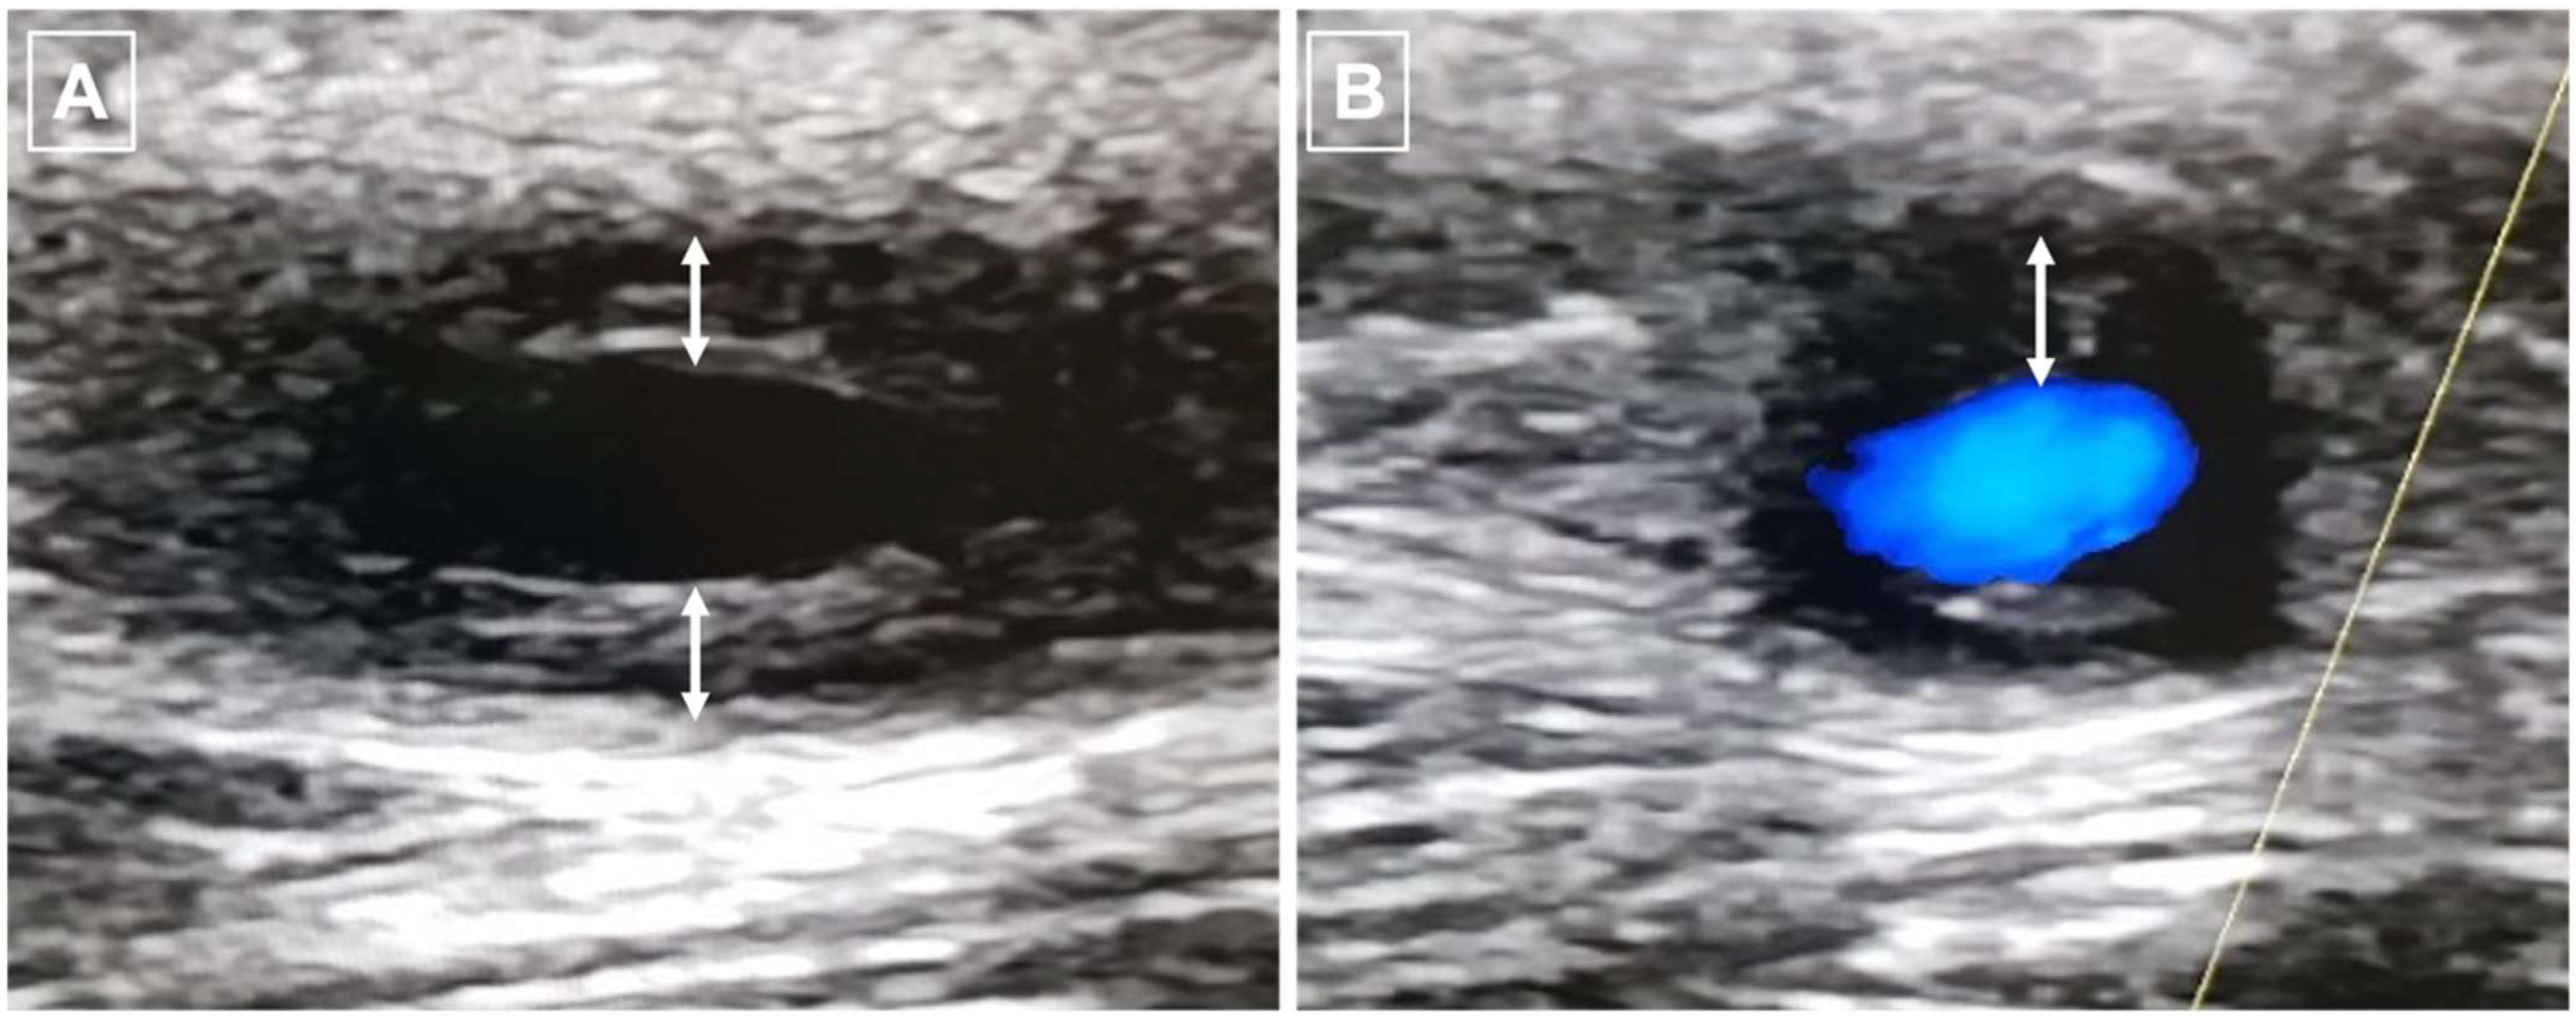

5.1. Ultrasound (US) Imaging

- Chrysidis, S.; Duftner, C.; Dejaco, C.; Schäfer, V.S.; Ramiro, S.; Carrara, G.; Scirè, C.A.; Hocevar, A.; Diamantopoulos, A.P.; Iagnocco, A.; et al. Definitions and Reliability Assessment of Elementary Ultrasound Lesions in Giant Cell Arteritis: A Study from the OMERACT Large Vessel Vasculitis Ultrasound Working Group. RMD Open 2018, 4, e000598. [Google Scholar] [CrossRef] [PubMed]